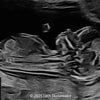

A 33-year-old nullipara with non-contributory medical history presented at 20 weeks, 6 days based on an early scan. Ultrasound revealed the following findings. There were no other apparent abnormalities. What is the most probable diagnosis?